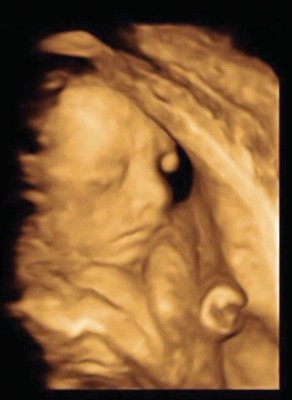

阿纬开心秀音波照宣布爱妻怀孕。 Lollipop@F的刘峻纬(阿纬)今年7月风光迎娶中菲行国际物流创办人千金钱文仪(豆豆),稍早阿纬在脸书分享喜讯,“多谢老天爸把你给了我,我已经准备好做一个‘爸爸’了”。他还开心表示这是最棒的生日礼物,也感谢辛苦老婆大人,并大方秀出女儿的超音波图。阿纬的好友杨奇煜则留言,“我要生个儿子去把姐姐”,鬼鬼(吴映洁)也兴奋地留言:“我是国句(际)小巨星干妈哈哈 。”